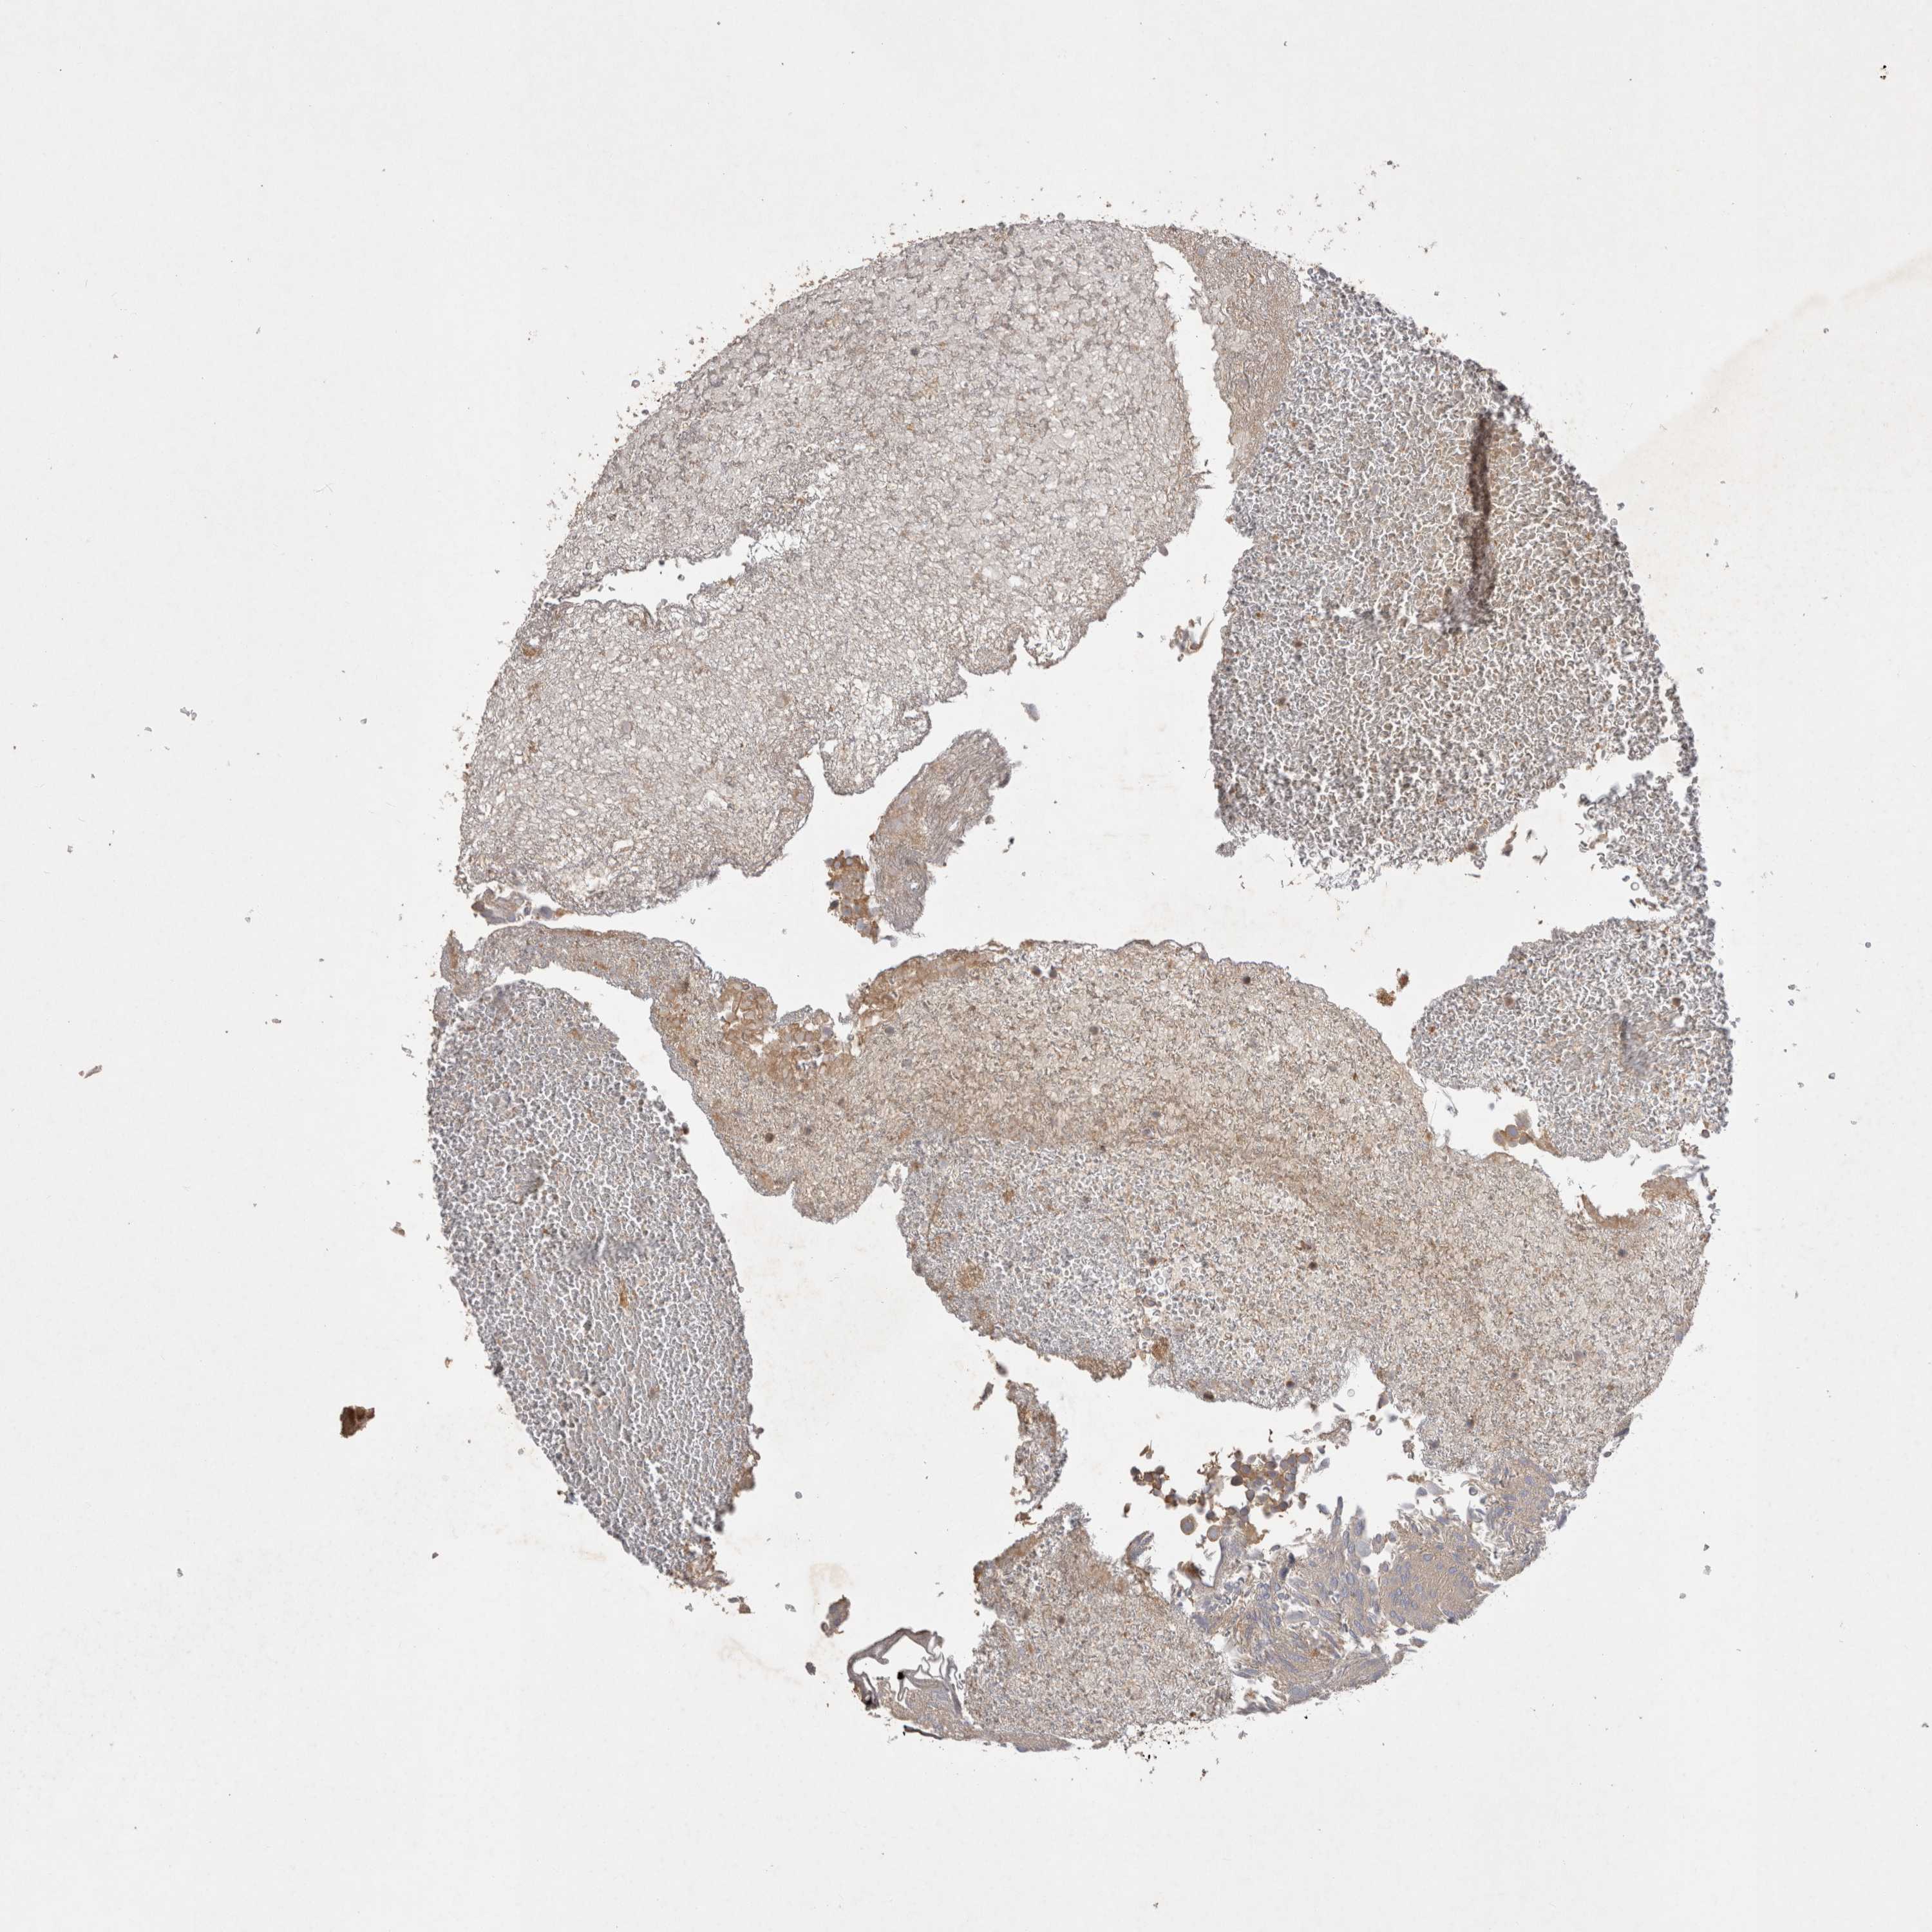

UROTHELIAL CANCER - Protein expressioni

A mouse-over function shows sample information and annotation data. Click on an image to view it in a full screen mode. Samples can be filtered based on level of antibody staining by selecting one or several of the following categories: high, medium, low and not detected. The assay and annotation is described here.

Note that samples used for immunohistochemistry by the Human Protein Atlas do not correspond to samples in the TCGA dataset.

Antibody stainingi

Antibody staining in the annotated cell types in the current human tissue is reported as not detected, low, medium, or high, based on conventional immunohistochemistry profiling in selected tissues. This score is based on the combination of the staining intensity and fraction of stained cells.

Each image is clickable and will lead to virtual microscopy that enables deeper exploration of all samples and also displays staining intensity scores, fraction scores and subcellular localization as well as patient and tissue information for each sample.

Antibody HPA024313

Antibody HPA027983

Antibody HPA028628

Urothelial carcinoma, Low grade